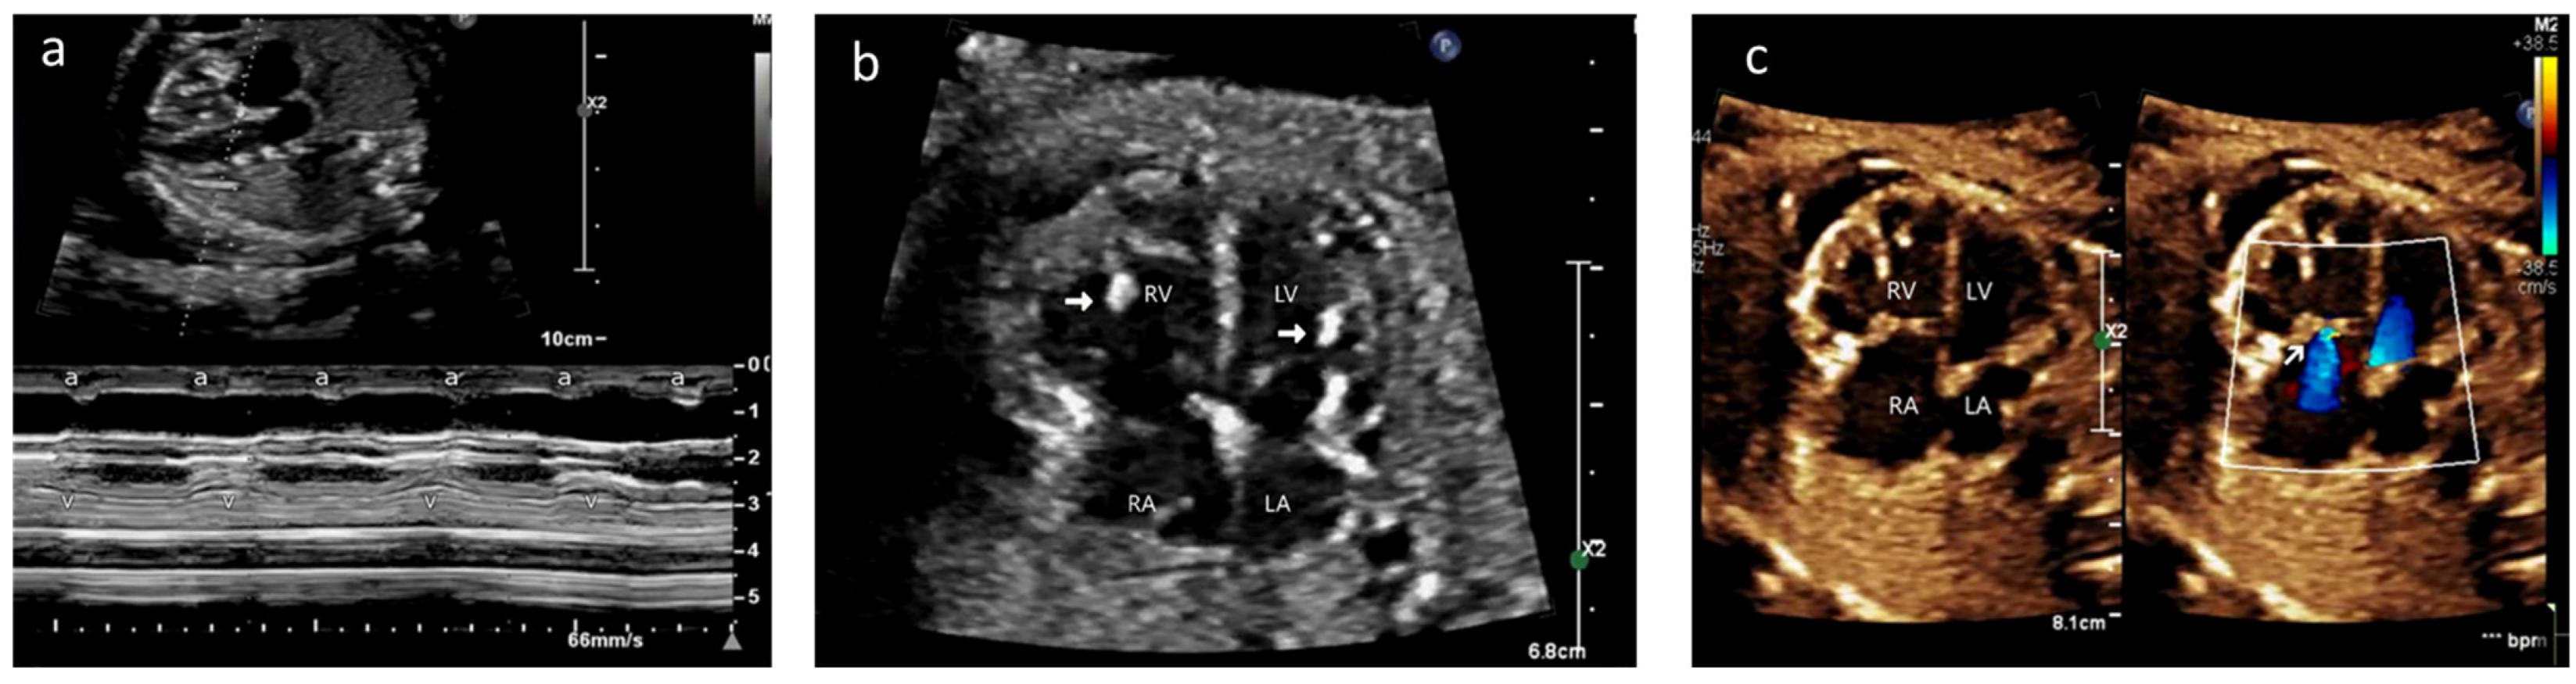

A 35-year-old gravida 2, para 1 mother was referred to our fetal cardiology center at 21 weeks of gestation for evaluation of fetal hydrops and bradycardia. An echocardiogram showed a ventricular rate of 74 bpm and an atrial rate of 144 bpm (Figure 1a). There was patchy hyperechogenicity of the atrial and ventricular walls, including the septum and chordae (Figure 1b/Video S1). The fetus had moderate tricuspid regurgitation (TR) and mild mitral regurgitation (MR), along with pleural and pericardial effusion, and a cardiovascular profile score of 8 (Figure 1c/Video S2).

Figure 1.

Case A: (a) M-mode echocardiogram showing atrioventricular dissociation; ‘a’ shows atrial contractions and ‘V’ shows ventricular contractions. (b) Antenatal echocardiogram, four-chamber view, showing hyperechoic papillary muscles (white arrow) in the left ventricle (LV) and right ventricle (RV). RA—right atrium, LA—left atrium. (c) Antenatal echocardiogram, four-chamber view, showing mild tricuspid regurgitation (white arrow) and no mitral regurgitation with normal atrioventricular valves.